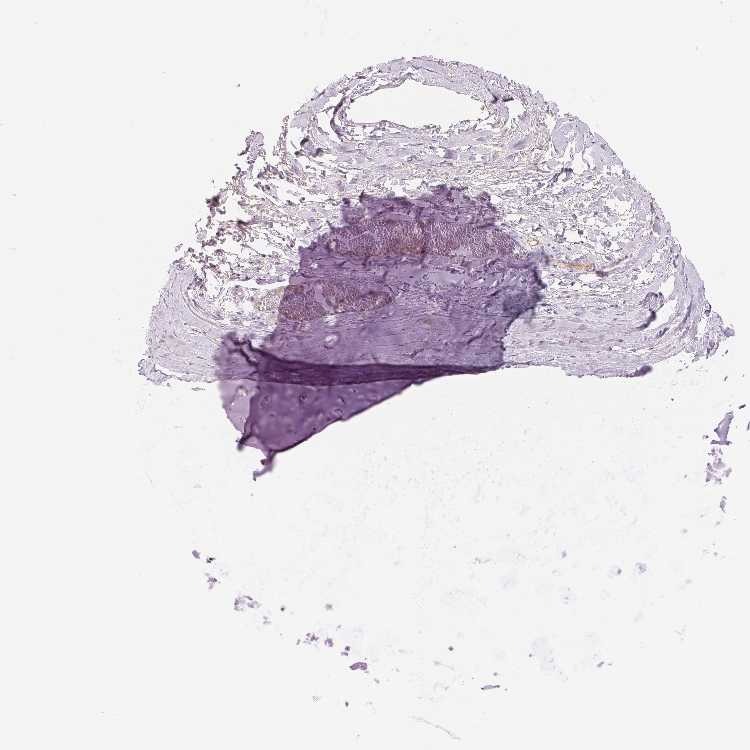

SOFT TISSUE 1 - Antibody stainingi

Antibody staining in the annotated cell types in the current human tissue is reported as not detected, low, medium, or high, based on conventional immunohistochemistry profiling in selected tissues. This score is based on the combination of the staining intensity and fraction of stained cells.

Each image is clickable and will lead to virtual microscopy that enables deeper exploration of all samples and also displays staining intensity scores, fraction scores and subcellular localization as well as patient and tissue information for each sample.

Antibody HPA062924

Chondrocytes Not detected

Fibroblasts Not detected

SOFT TISSUE 2 - Antibody stainingi

Peripheral nerve Not detected